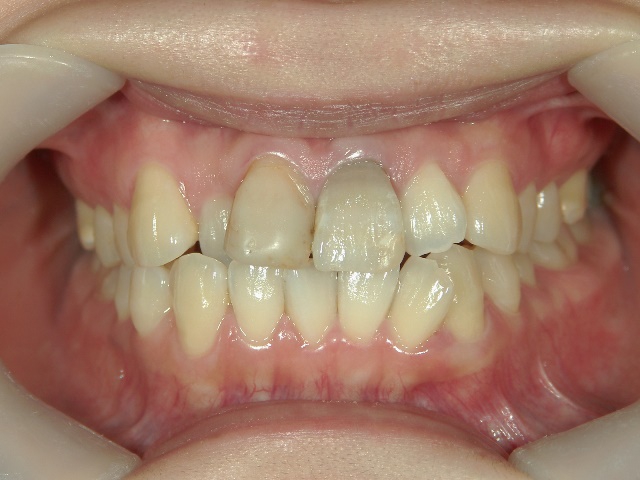

矯正歯科 治療前矯正歯科 治療前

矯正歯科 治療後矯正歯科 プチワイヤー矯正 治療後矯正歯科(プチワイヤー矯正)治療後

no.37_7548_治療前_右.JPGno.37_7548_治療前_正面.JPGno.37_7548_治療前_左.JPG

no.37_7548_治療後_右.JPGno.37_7548_治療後_正面.JPGno.37_7548_治療後_左.JPG